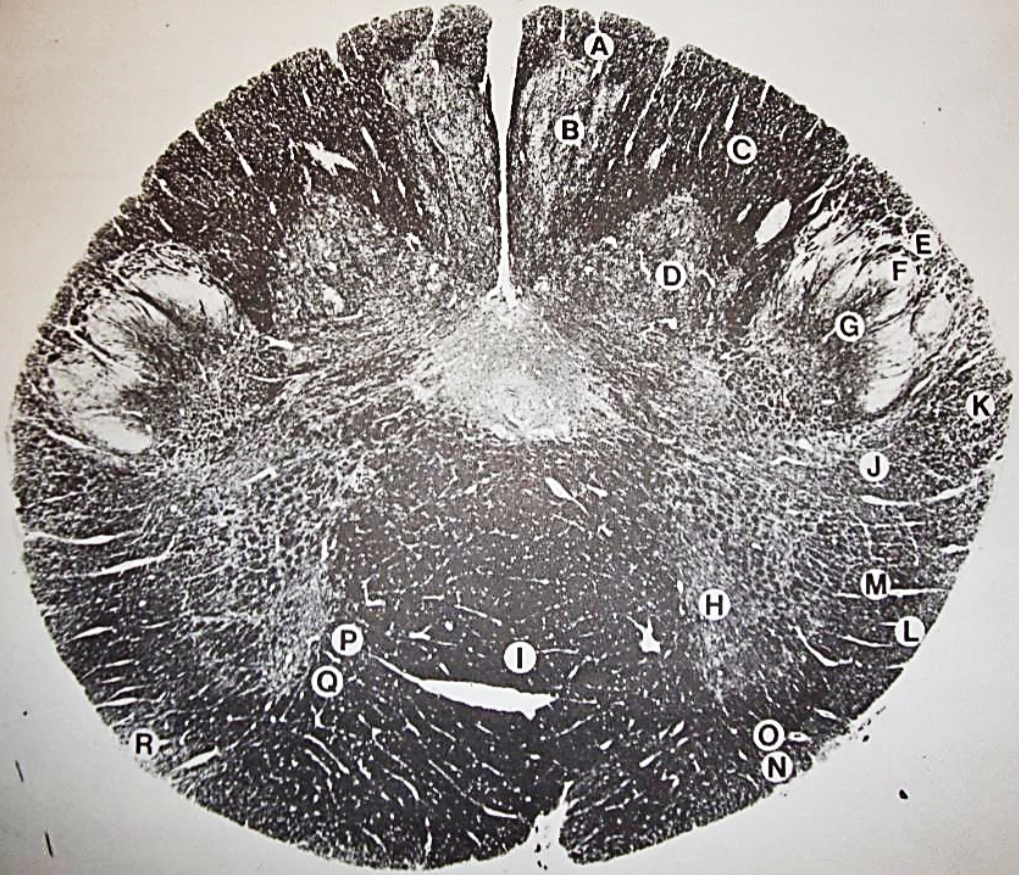

A

posterior median sulcus

B

posterior intermediate sulcus

C

anterior median fissure

D

gracile fasciculus

E

Gracile nucleus

F

fasciculus cuneatus

G

spinal trigeminal tract

H+I collectively

spinal trigeminal nucleus

J

Accessory nucleus

K

pyramidal decussation

L

lateral corticospinal tract

M

rubrospinal tract

N

posterior spinocerebellar tract

O

anterior spinocerebellar tract

P

lateral spinothalamic tract

Q

anterior spinothalamic tract

R

lateral vestibulospinal tract

S

medial longitudinal fasciculus

T

tectospinal tract

U

central canal